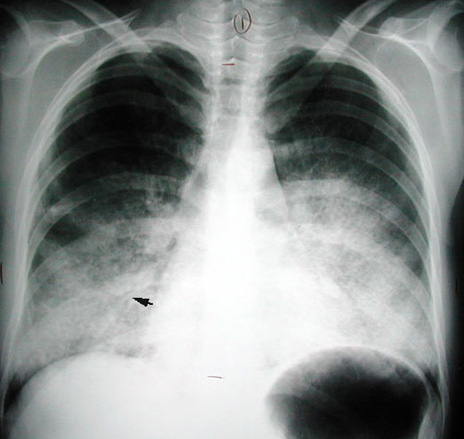

Alveolar Proteinosis

Butterfly distribution.

Air bronchogram (arrowhead).

Patient has chronic diffuse bilateral alveolar disease.